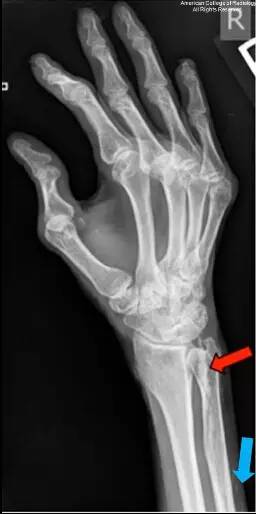

图 2 为右手斜位,可见临近尺骨近端一线性钙化(蓝色箭头)。腕部背侧仍可见钙化(红色箭头)。第一和第三掌指关节可见半脱位